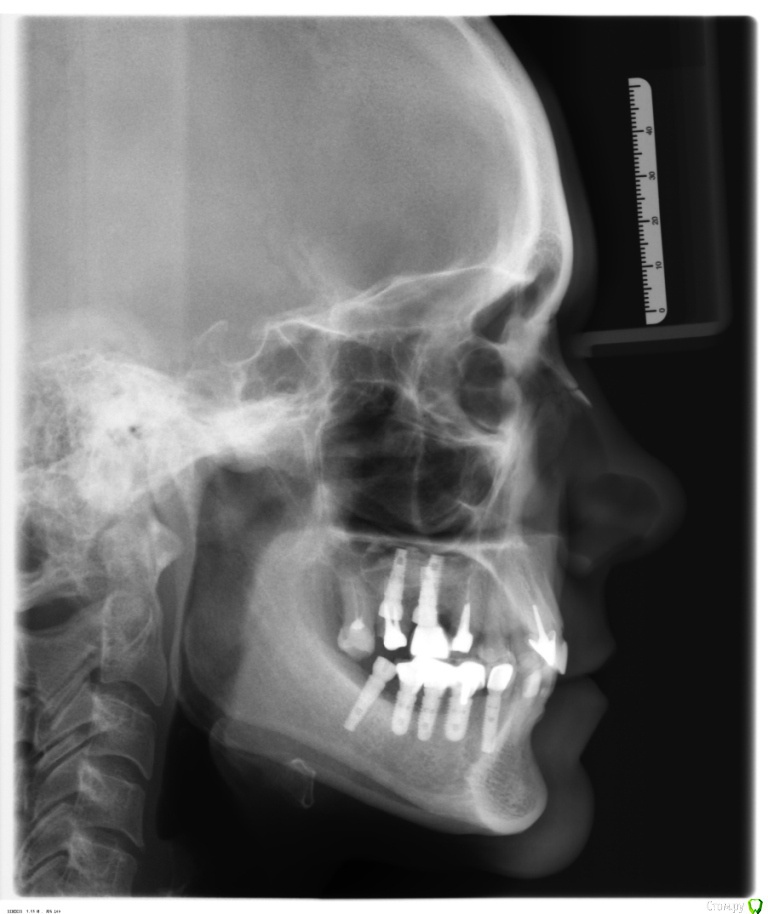

Cheremukha Опубликовано 15 апреля, 2016 Поделиться Опубликовано 15 апреля, 2016 Здравствуйте уважаемые доктора! Буду очень признательна за консультацию и обозначение тактики лечения. Субъективные жалобы: периодически возникающий глухой стук слева при жевании, хруст справа при открывании рта. Жжение языка. Боль в области уха справа. Головные боли в затылке (ежедневные) и сдавливание в области основания черепа. Боли и хруст появились после удаления зубов и имплантации (5 имплантов) 2 года назад. Потом последовало не совсем удачное протезирование, которое как раз привело к появлению щелчков и жжению языка. Я сменила ортопеда. Новый доктор убрал 10 коронок на коренных зубах и поставил временные коронки с завышением прикуса. На них у меня возникли сильные боли в челюстях, ухе, голове, я не могла их выдержать и попросила их снять, что доктор и сделал. Уже месяц я хожу без коронок. Сейчас у меня отсутствуют: слева вверху и внизу концевые зубы начиная с 5-го и справа внизу концевые зубы начиная с 4-го. Стоят абатменты и вкладки, а коронок на них нет. МРТ (3-х месячной давности): Частичная вентральная дислокация диска правого ВНЧ сустава с полной репозицией. Артроз левого ВНЧ сустава 0-1ст. Малая частичная вентральная дислокация диска с полной репозицией при открывании рта и формированием частичной медиальной дислокации диска. МР-признаки функциональной перегрузки правой латеральной крыловидной мышцы. Делала боковую ТРГ, заключение не дали, снимок прилагаю. Так же прилагаю орто-снимок. Ортопед, у которого я была на консультации предлагает поставить временные коронки, которые он будет подтачивать под мое удобное положение челюсти, а потом запротезируют постоянными коронками. Скажите пожалуйста, достаточно ли в моем случае протезирования без ношения капы? Какая тактика лечения наиболее приемлема в моем случае? З.Ы. Еще сложность в том, что у меня стоят импланты Астра и Лико. Оказалось, что очень непросто найти в Москве ортопеда, работающего на обоих системах. Ссылка на комментарий